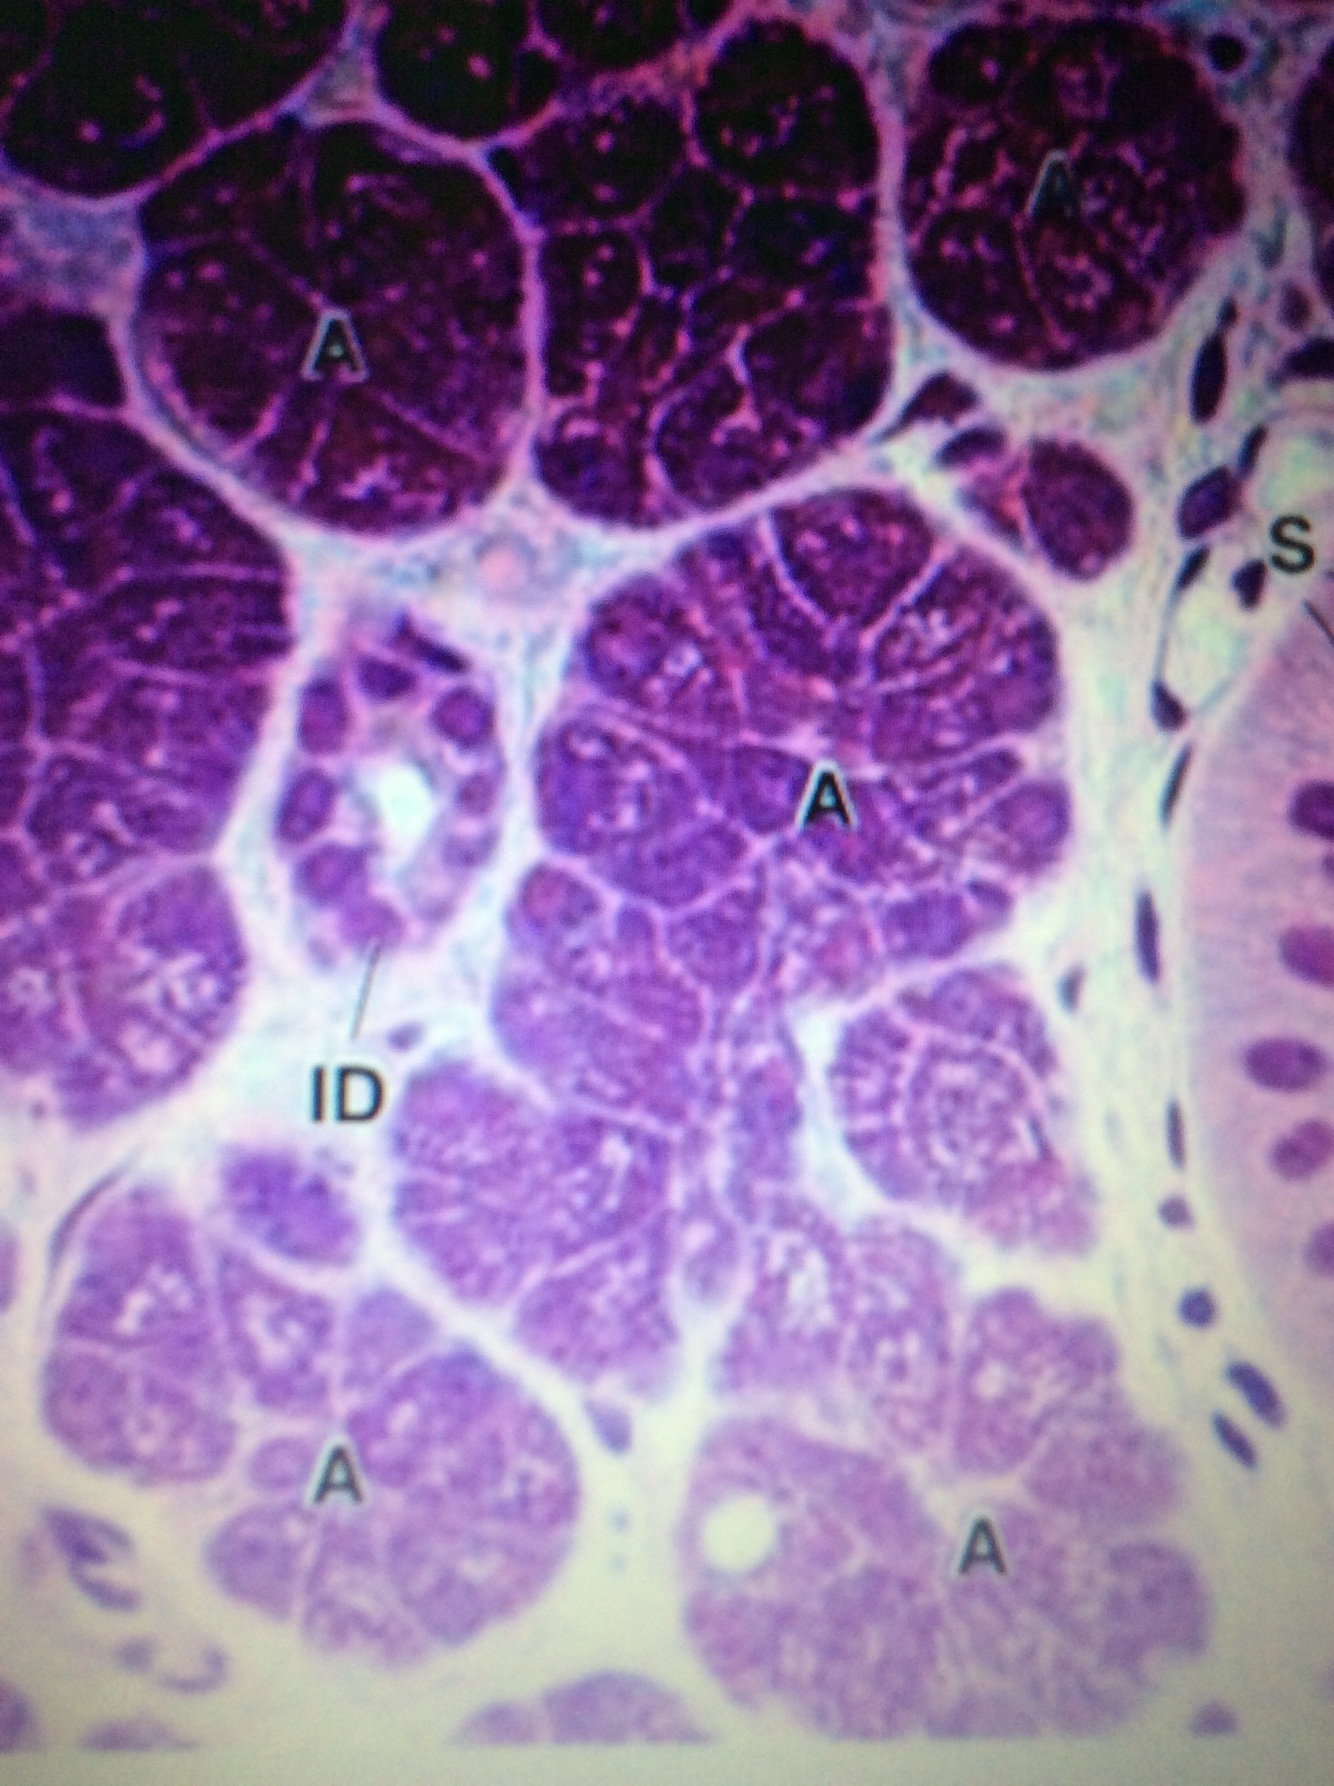

What type of epithelial cells are these? Where are they found? What is its function?

Serous acini - simple cuboidal epithelium

Found in the salivary glands - parotid (all serous) and sub-mandibular glands (mixed but produces 75% of saliva secretion)

They secrete serous saliva into ducts which travel to the buccal cavity.